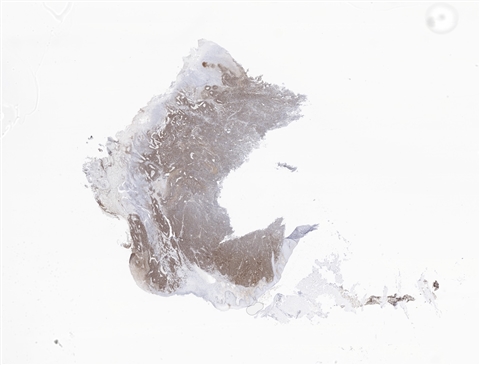

患者详情: 患者4月前开始出现上腹胀痛不适,进食后加重,伴梗咽感,不伴恶心呕吐、腹泻便秘、畏寒发热等不适,因症状持续遂当地医院就诊,行电子胃镜检查示:贲门-胃体CA? 胃镜:贲门、胃底见一大小约2.0*1.5厘米不规则溃疡面,覆污苔,取检质脆易出血,粘液湖清。 CT:贲门胃底区壁不规则增厚并软组织肿块影,边界不清,突向腔外,邻近胃周脂肪毛糙,增强呈明显不均匀、持续性强化,胃周结构层次毛糙,胃周见稍大淋巴结,呈中等欠均匀强化。贲门胃底区增厚并肿块,胃周浸润,请结合胃镜检查。 肿瘤标志物:CEA、CA199、CA125均正常

大体所见: 全胃切除标本:大弯长24cm,小弯长15cm,附网膜14*11.5*5cm,距贲门切缘2cm处于小弯侧见4.5*4.5*2.5cm溃疡性肿物,切面灰白色,实性,质硬,肉眼侵及全层。

医院: 南昌大学第二附属医院